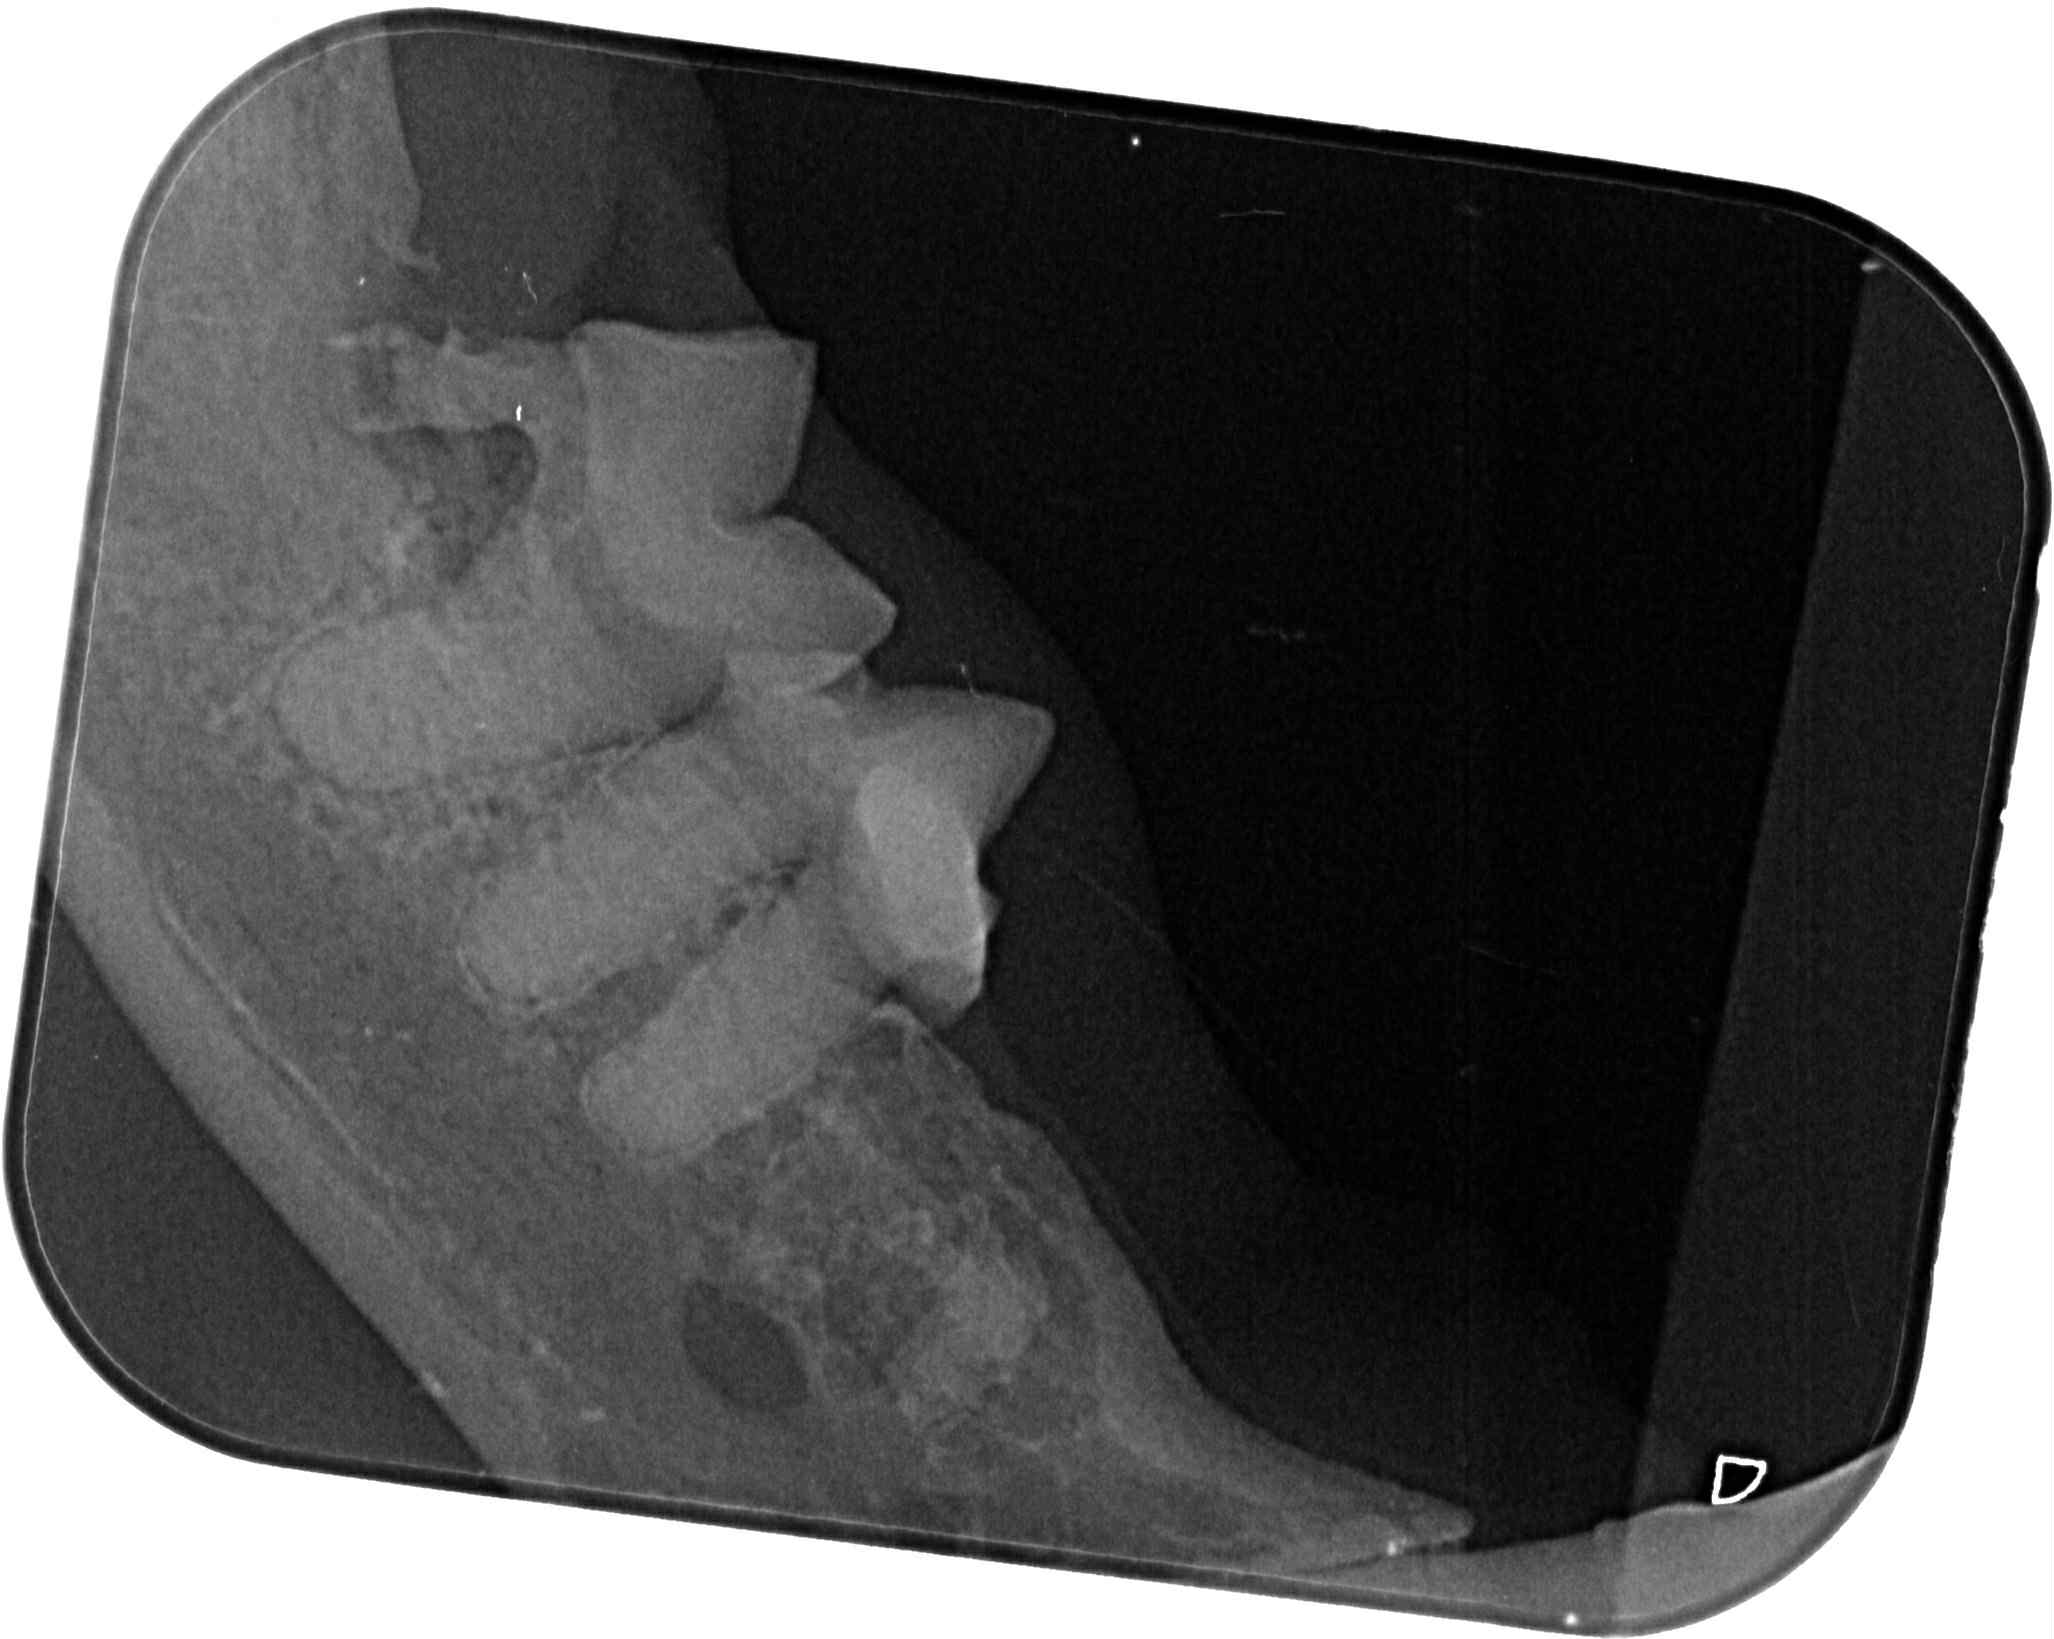

原安置於苗栗貓屋的乖豹於2025年10月與其他貓咪全數移回台北安養之家後發現體型逐漸消瘦,且背上有一顆顆肉瘤以及牙齒有鬆動的狀況,於是安排2025年11月28日於沐恩看診,醫師表示整體狀況還不錯,背上粉瘤為良性,主要是牙結石嚴重,研判體重下滑應與此有關,需盡快安排牙周手術。後再於同年12月17日進行牙周手術,後面的臼齒、2顆下門牙及上顎那一顆不好犬齒都移除,保留下面兩顆犬齒,同時背部腫塊偏良性因此暫不切除。本筆醫助是自2025年11月28日至2025年12月17日間於沐恩醫院的費用,包含看診各項檢驗、牙周手術及用藥。

2025/11/28 乖豹 沐恩看診 林院長

一、看診說明

整體都不錯,主要是牙齒結石嚴重,

盡快安排時間處理,

變瘦很多應跟牙齒有關。

2025/12/17乖豹 沐恩牙周手術

手術還算順利,血壓稍微比較不容易穩定,

目前後面的臼齒、2顆下門牙及上顎那一顆不好犬齒都移除了,

下面兩個犬齒的狀況還不錯,所以還是保留下,為了縮短麻醉時間。

皮膚的腫塊看起來外觀偏良性,所以沒切除。

目前看起來,他的咬合是比較正常的,

有可能不會咬到上顎,因為本來就已經有一邊沒有上門牙了,

理論上不會對生活有影響,另外他的下顎聯合原本就是鬆的,

所以會一個伸縮的彈性,對上顎影響相對減少

下顎聯合鬆的意思就是兩側下顎骨會些微的上下晃動。